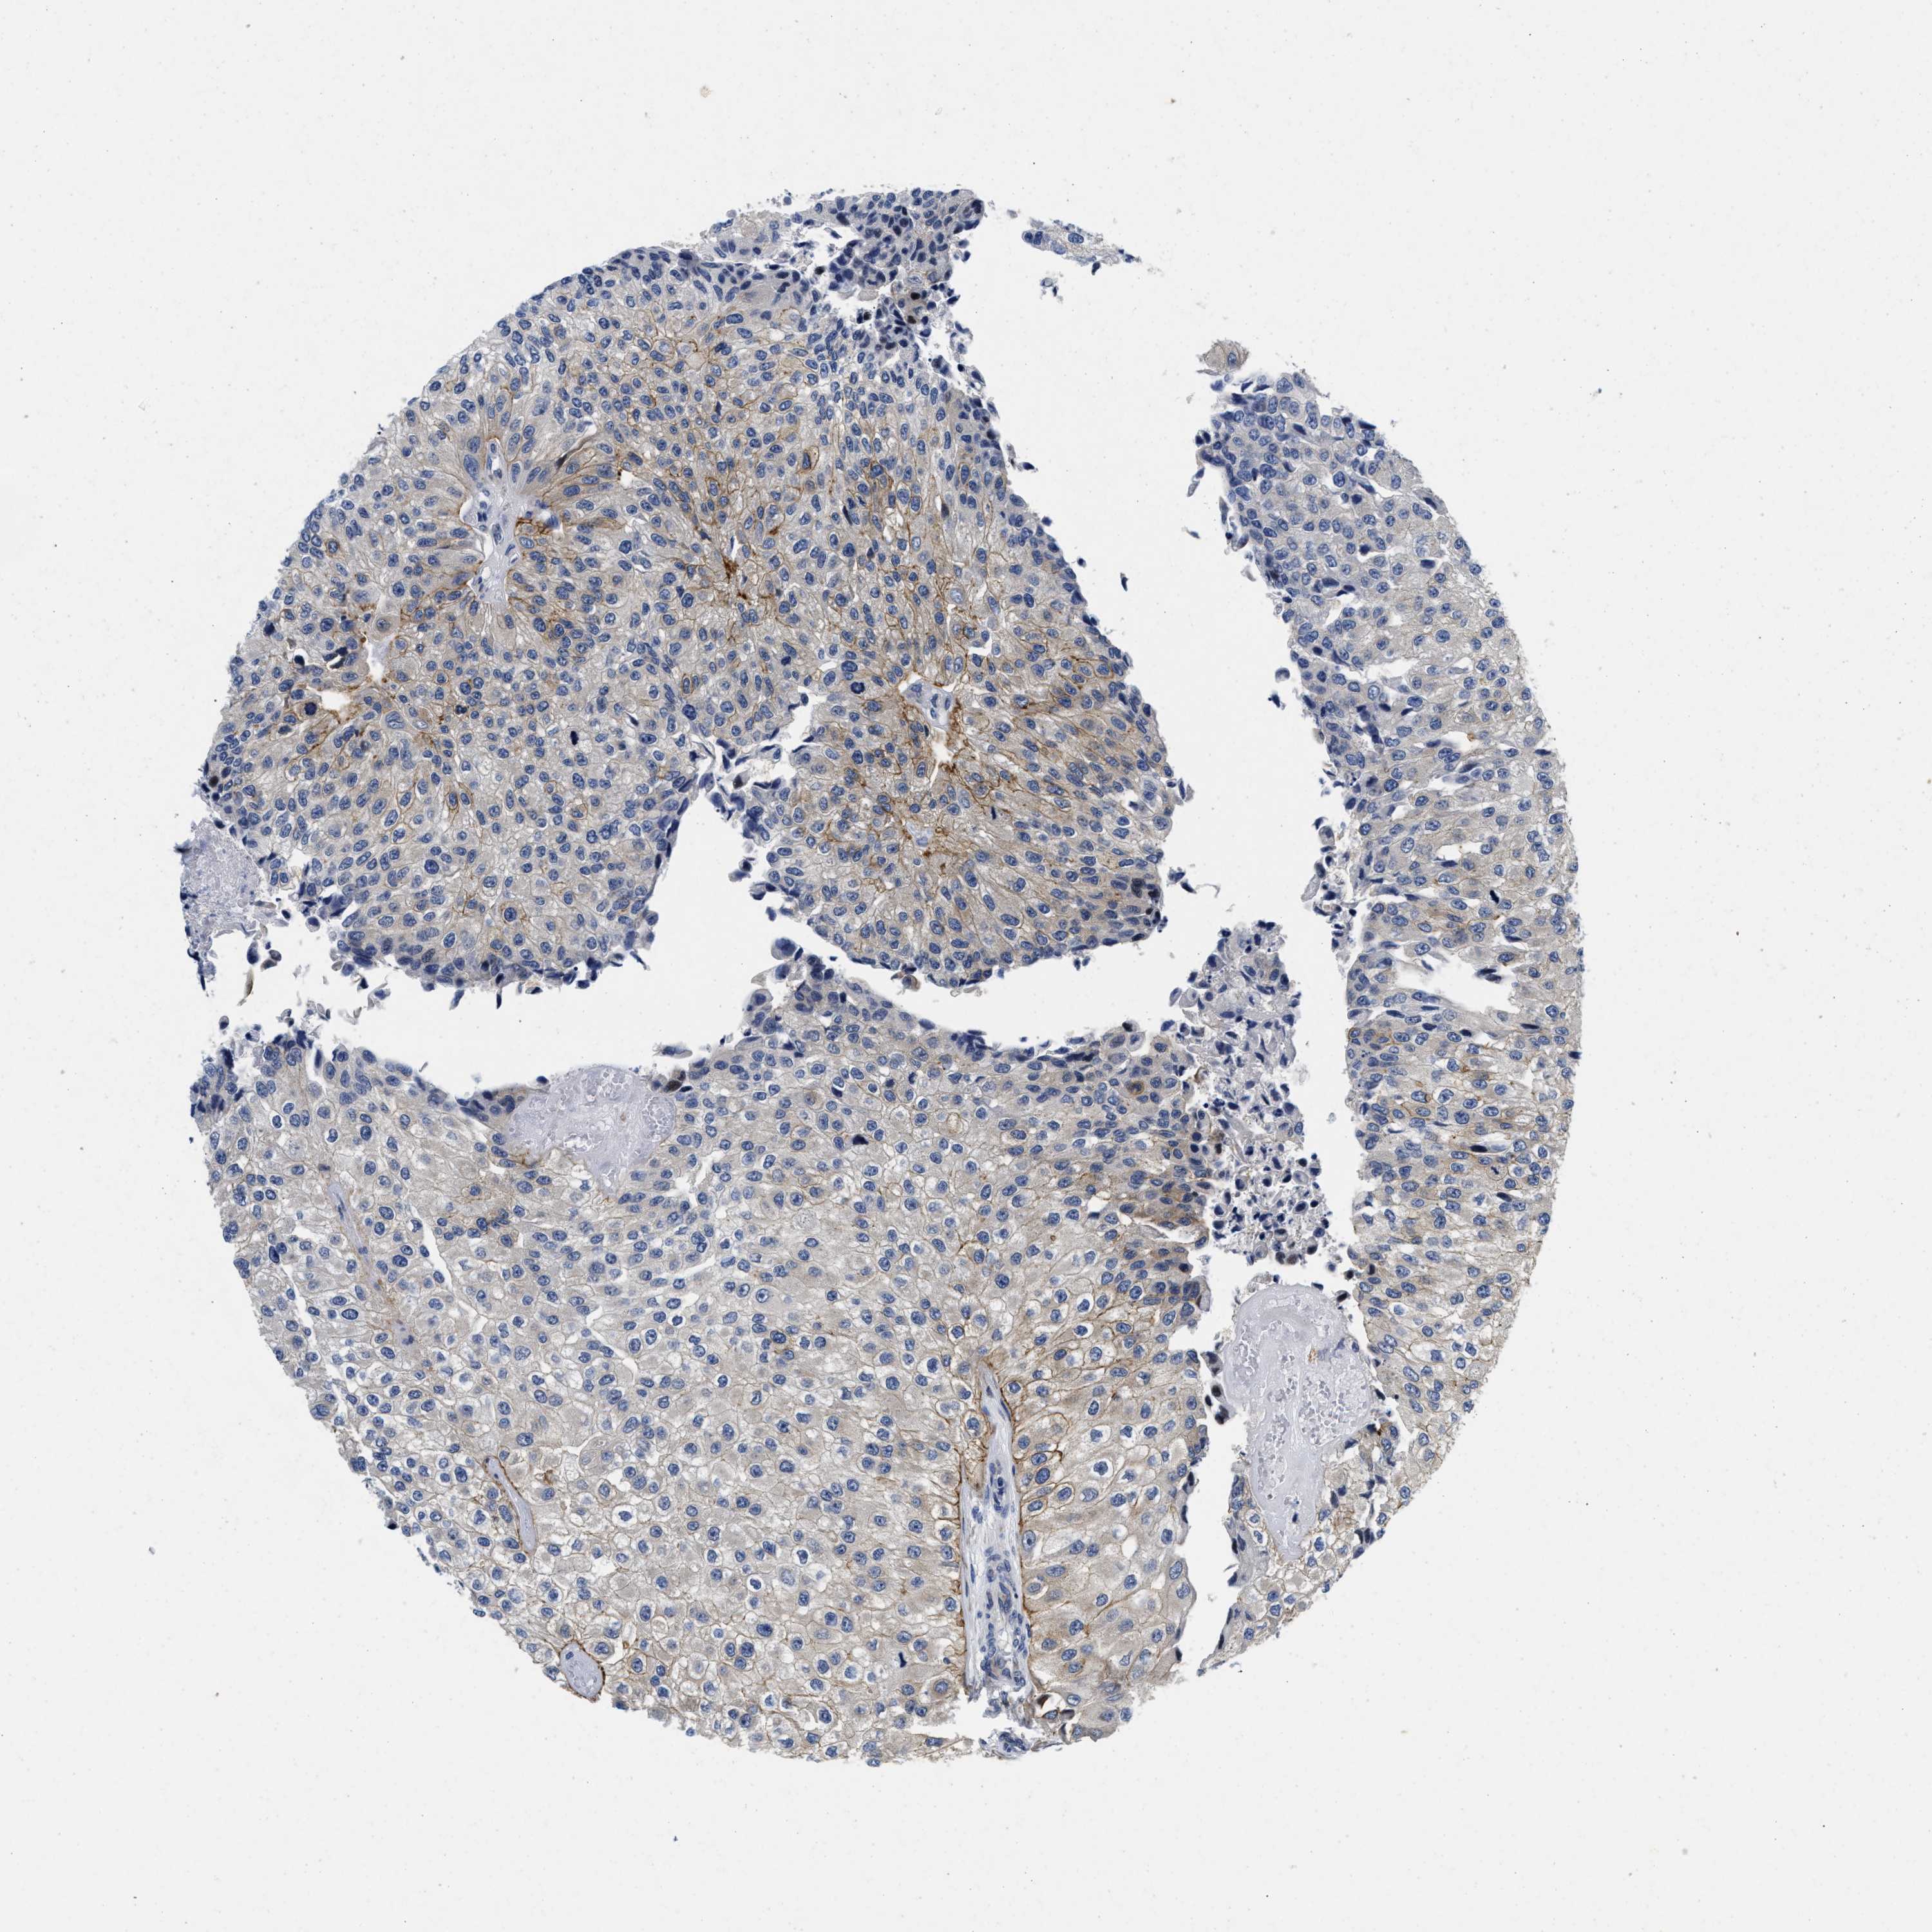

UROTHELIAL CANCER - Protein expressioni

A mouse-over function shows sample information and annotation data. Click on an image to view it in a full screen mode. Samples can be filtered based on level of antibody staining by selecting one or several of the following categories: high, medium, low and not detected. The assay and annotation is described here.

Antibody stainingi

Antibody staining in the annotated cell types in the current human tissue is reported as not detected, low, medium, or high, based on conventional immunohistochemistry profiling in selected tissues. This score is based on the combination of the staining intensity and fraction of stained cells.

Each image is clickable and will lead to virtual microscopy that enables deeper exploration of all samples and also displays staining intensity scores, fraction scores and subcellular localization as well as patient and tissue information for each sample.

Antibody HPA007256

Antibody HPA028732

Staining

High

Medium

Low

Not detected

Intensity

Strong

Moderate

Weak

Negative

Quantity

>75%

75%-25%

<25%

None

Location

Nuclear

Cytoplasmic/membranous

Cytoplasmic/membranous,nuclear

Urothelial carcinoma, Low grade

Urothelial carcinoma, High grade